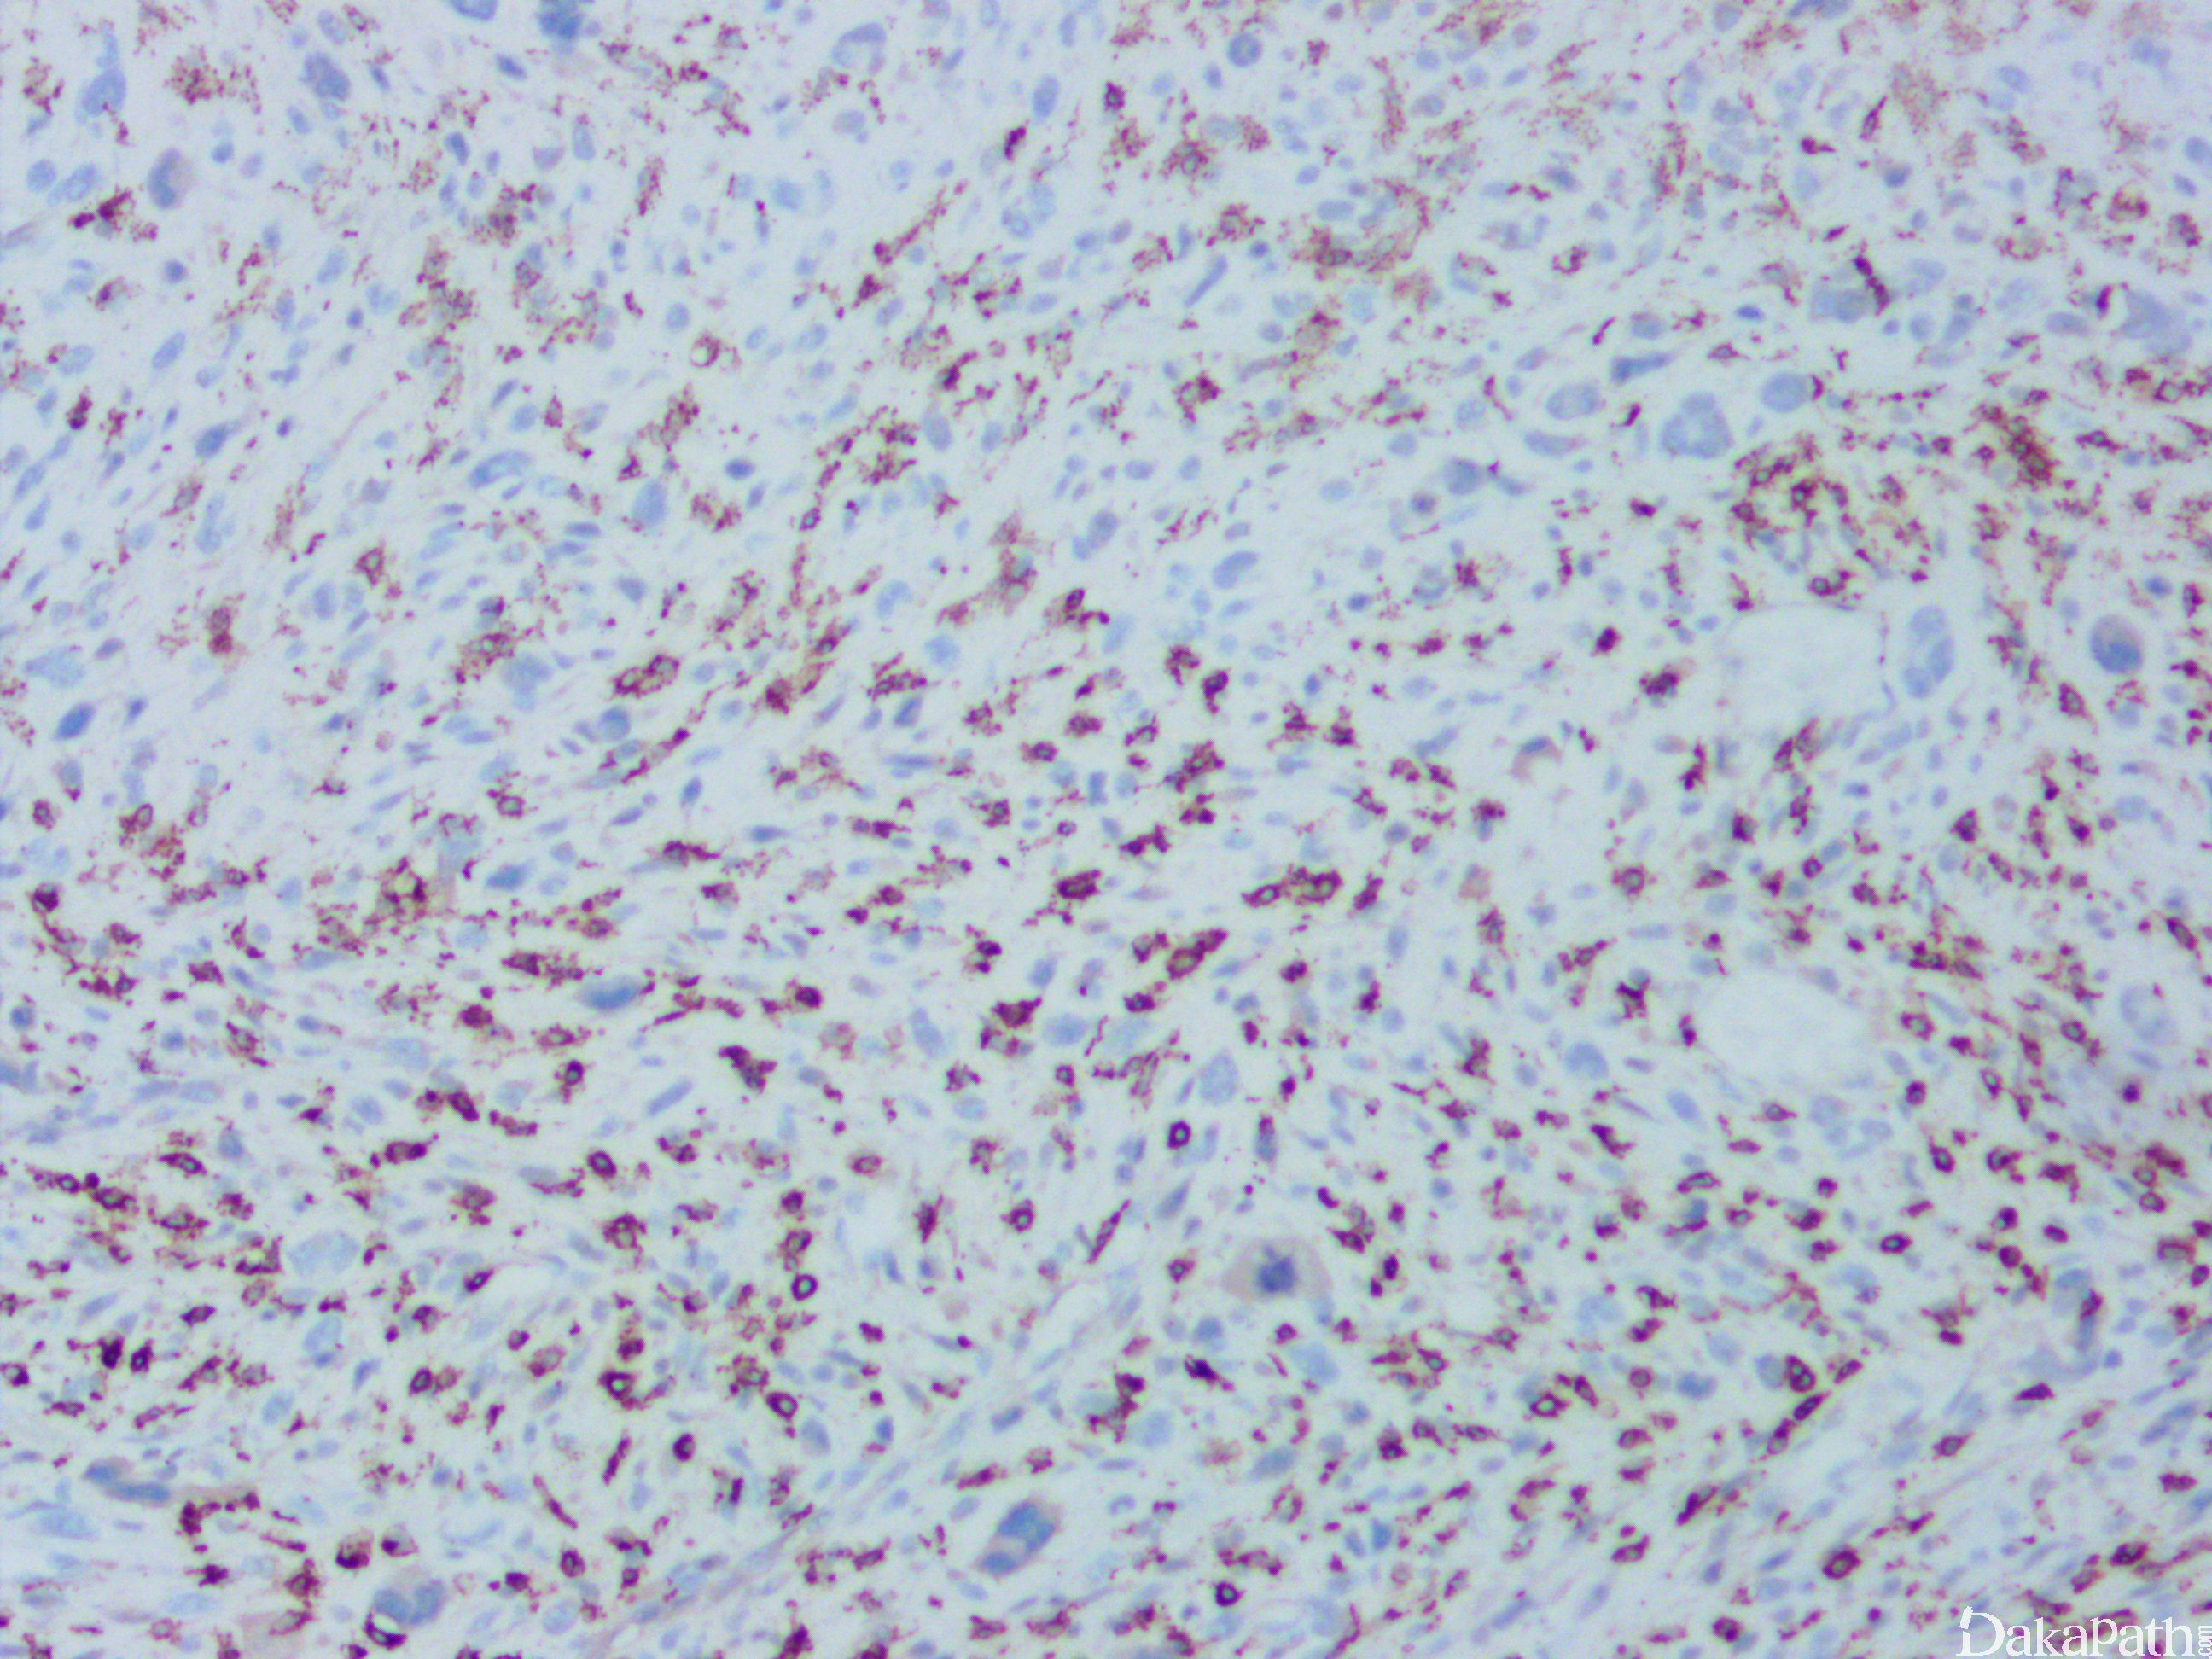

特殊染色和免疫组织化学:vimentin、CD68 阳性;

无特征性标记,vimentin、CD68 阳性;actins、结蛋白和 h-caldesmon 可局灶阳性,偶可表达 CK 和 EMA,少数病例还可局灶表达 S-100,不表达 HMB45,常见 P53 过表达和 Rb1 蛋白表达缺失,其诊断往往是排除性诊断。